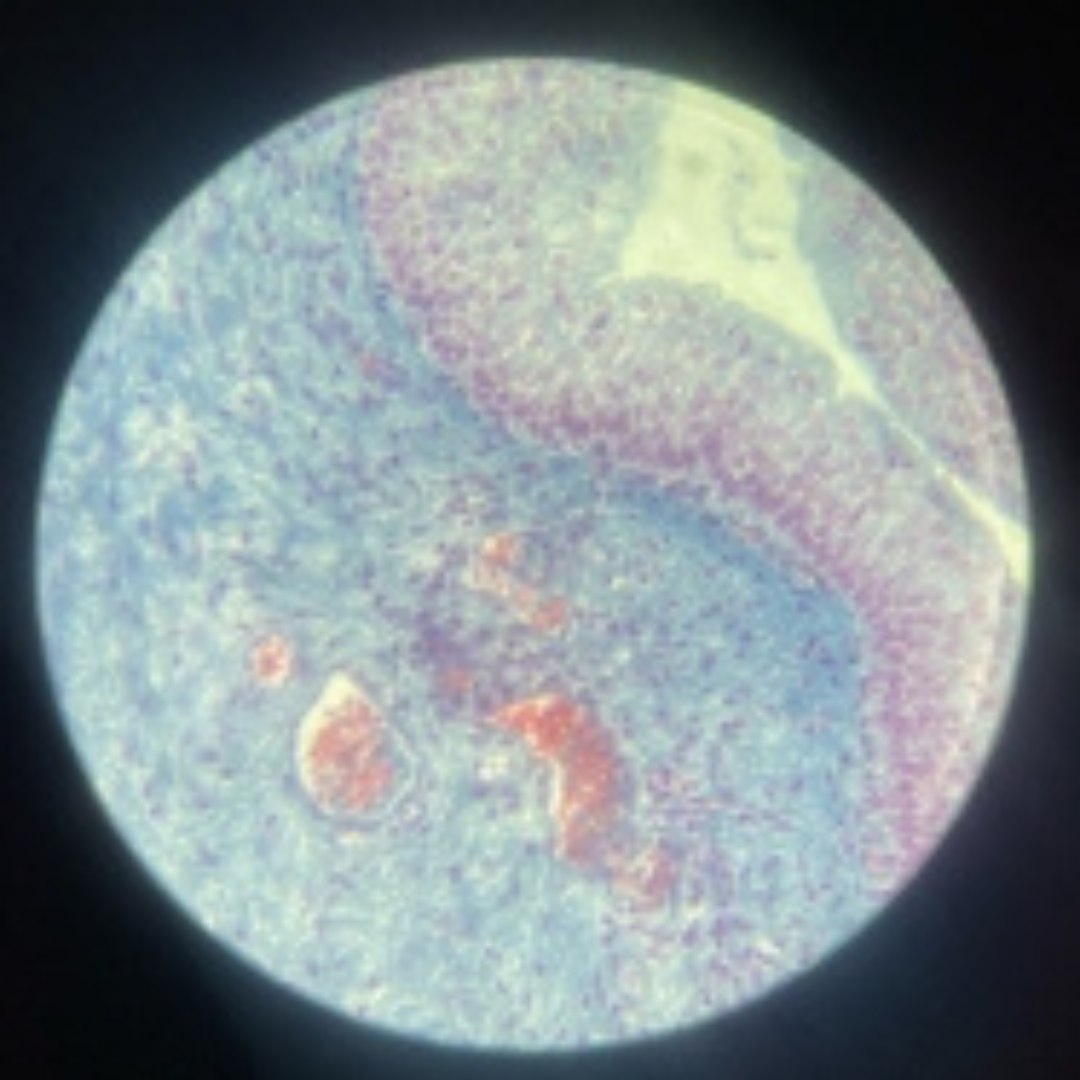

Reticular Connective Tissue (Lymph Node)

Kidneys (Nephron)